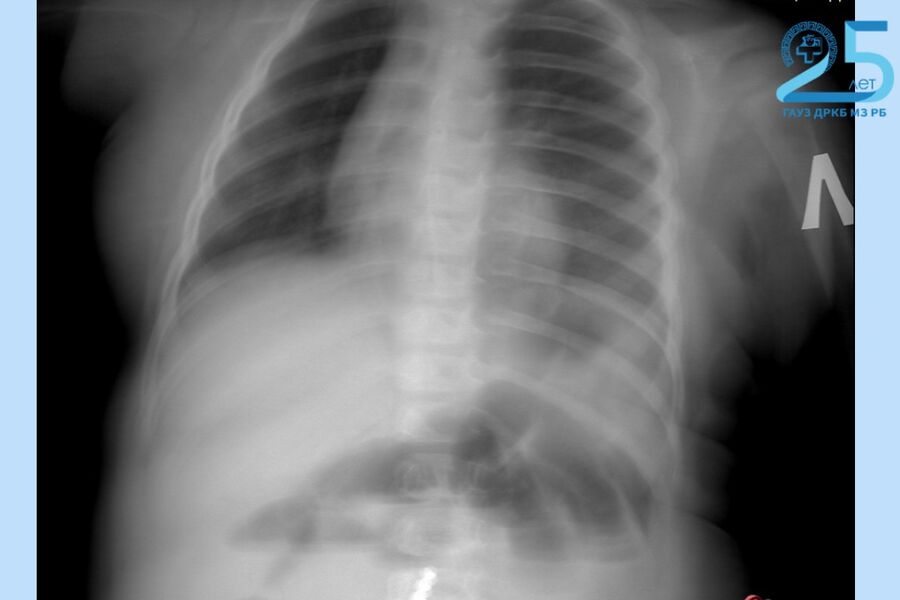

Маленький пациент поступил в больницу с приступами рвоты в тяжелом состоянии. Рентген показал множество инородных тел в желудочно-кишечном тракте. Выяснилось, что несовершеннолетний наглотался магнитных шариков от игрушки.

«Нам удалось удалить девять магнитов эндоскопически (ФГДС). Однако остальные мигрировали по кишечнику, вызвав перфорацию. Петли тонкой, сигмовидной и слепой кишки слиплись между собой из-за магнитного притяжения», — рассказал хирург-эндоскопист ДРКБ Булат Шагдаров.

Хирурги провели открытую операцию, из-за притянувшихся друг к другу магнитов им пришлось удалить поврежденный участок тонкой кишки. Врачи также ушили свищи и извлекли аппендикс, куда опустилась часть магнитов. Сейчас ребенок переведен из реанимации в обычное отделение, его состояние оценивается как стабильное.